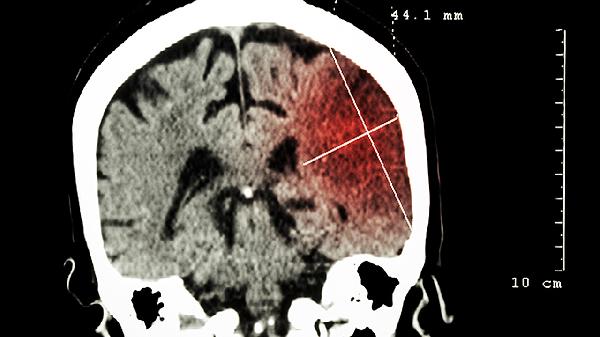

2、检查技术局限可能影响结果。常规超声检查的分辨率有限,难以发现细微的颅骨发育异常。高分辨率超声或核磁共振成像MRI能够提供更清晰的图像,有助于准确诊断无脑儿。选择具备先进设备的医疗机构进行检查,可提高诊断的可靠性。

无脑儿产检能查出来,主要通过超声检查、血清学筛查、羊水穿刺、无创DNA检测、核磁共振等方式进行诊断。 1、超声检...